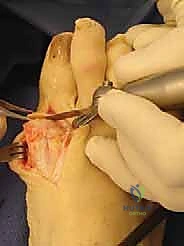

4. المحاذاة والتثبيت (الزاوية الذهبية)

يتم وضع العظمتين معاً في زاوية محددة بدقة شديدة:

* انثناء ظهري (Dorsiflexion): لتسمح للقدم بالتدحرج أثناء المشي وارتداء أحذية ذات كعب بسيط.

* زاوية أروح (Valgus): لتتوازى مع الأصابع الأخرى وتمنع احتكاك الإبهام بالحذاء.

بمجرد الوصول للزاوية المثالية، يقوم الدكتور هطيف بتثبيت العظمتين باستخدام أحدث التقنيات العالمية، والتي غالباً ما تشمل شريحة من التيتانيوم ومسامير ضاغطة (Titanium Plate and Compression Screws). هذا التثبيت القوي يسمح بالتحام العظمين ليصبحا عظمة واحدة صلبة خالية من الألم.